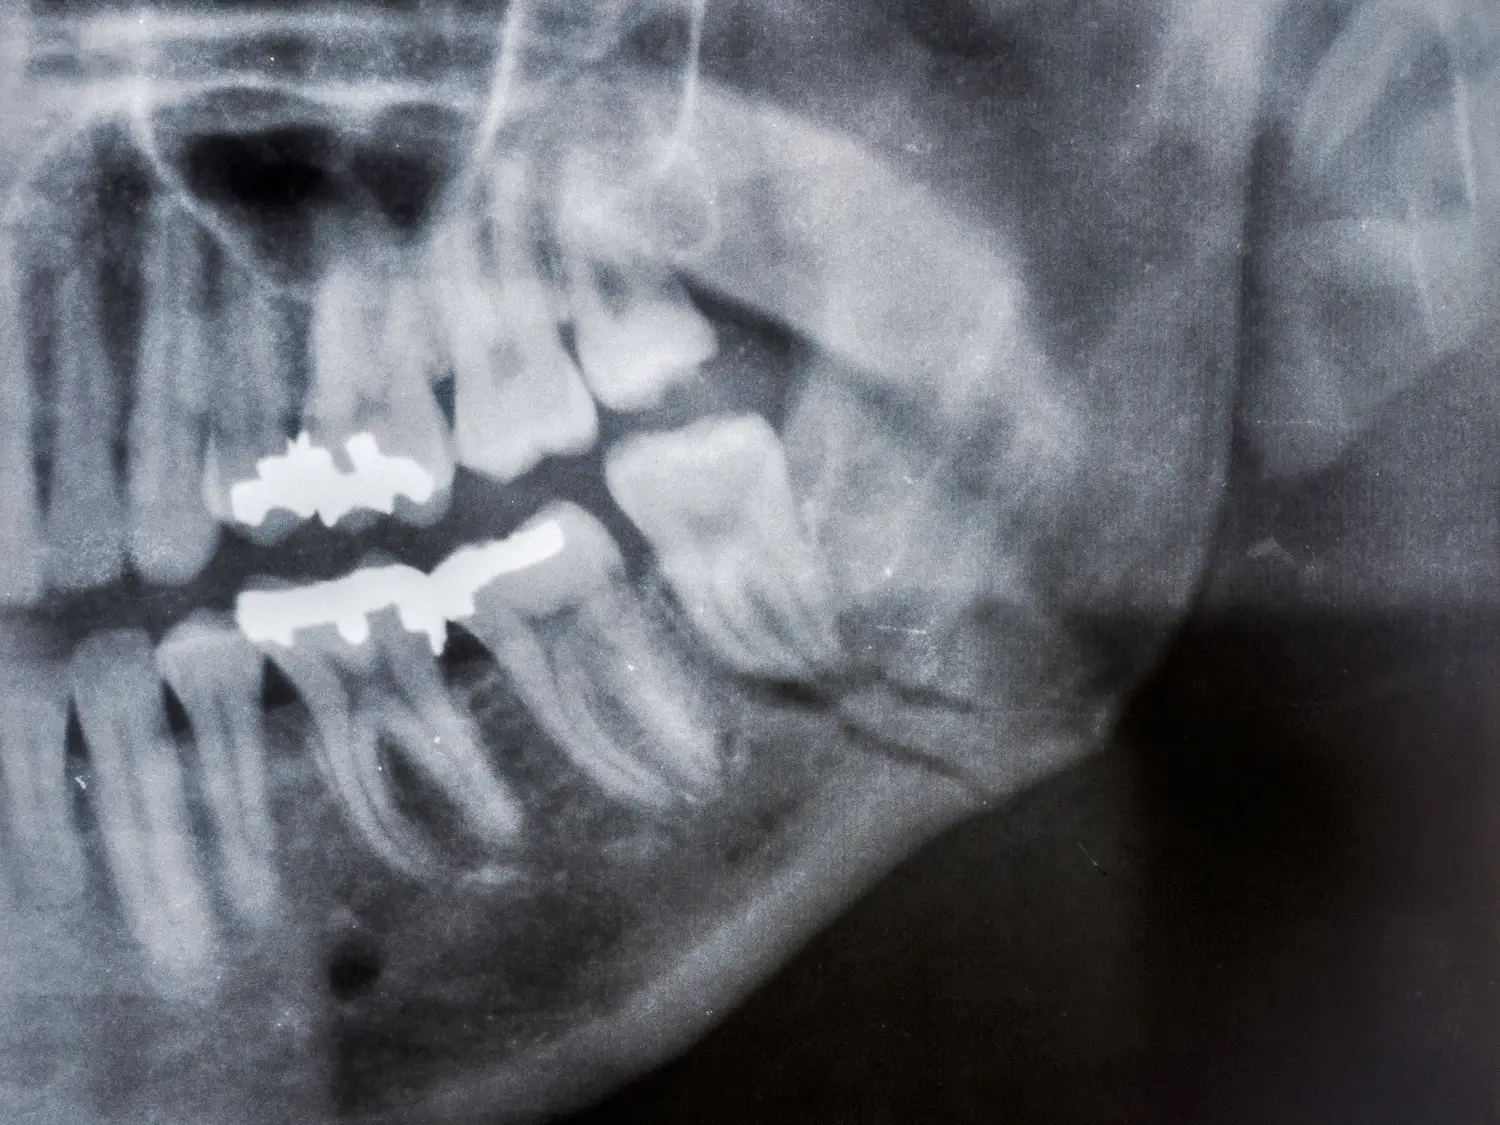

كسور وإصابات الوجه والفكين

علاج الكسور الناتجة عن الحوادث أو الإصابات، بما يشمل عظام الفك، والخد، ومحجر العين، وأيضًا تركيب شرائح ومسامير الوجه والفكين.